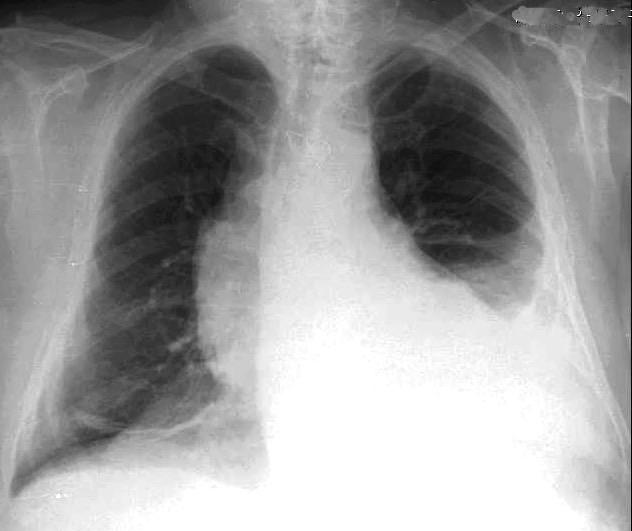

Marzo 2014: Perforación longitudinal distal secundaria a episodio de vómito (síndrome de Boerhaave). Derrame pleural izdo. que evoluciona a empiema.

Wang C-T et al. Tension hydropneumothorax in a Boerhaave syndrome patient: A case report . World J Emerg Med, 2021. Katabathina V et al. Nonvascular, nontraumatic mediastinal emergencies in adults:a comprehensive review of imaging findings. Radiographics. 2011.